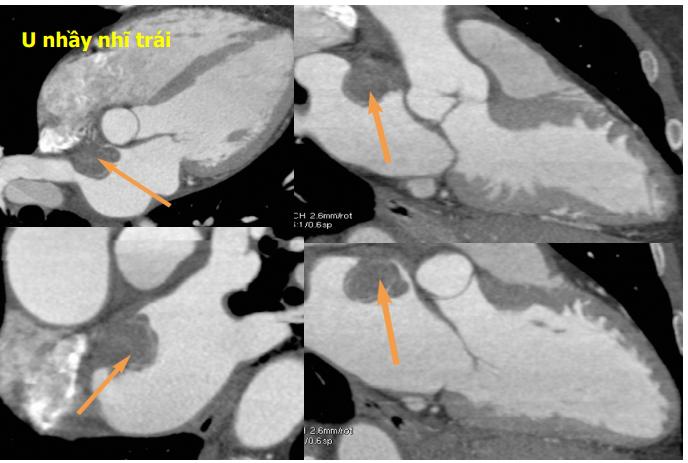

Ngoài ra còn một số căn nguyên đột quỵ do tim ít gặp hơn rung nhĩ như : còn lỗ bầu dục, sa vale 2 lá, u nhầy ở tim, viêm nội tâm mạc nhiễm trùng.